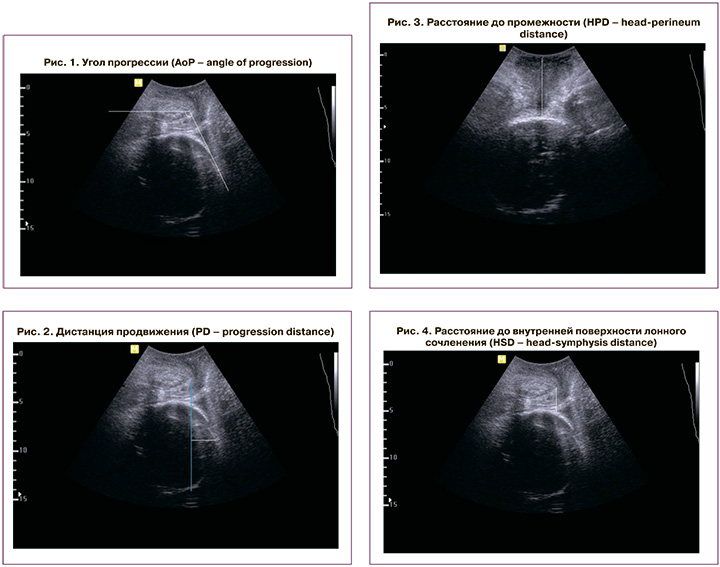

С помощью УЗИ проводили оценку 4 показателей, которые, по данным литературы, наиболее часто используются для характеристики течения родового акта [2, 9, 10]: угол прогрессии (AoP – angle of progression) измеряли при трансперинеальном продольном сканировании. Датчик устанавливали по средней линии лонного сочленения, чтобы его изображение располагалось горизонтально. Первый вектор строили от нижнего до верхнего края лонного сочленения, второй – от нижнего края лона по касательной к контуру головки плода (рис. 1) [8]; дистанцию продвижения (PD – progression distance) измеряли трансперинеально при продольном сканировании. Изображение лонного сочленения выводили горизонтально, как при измерении угла прогрессии. Первый вектор проводили вертикально вниз от нижнего края лонного сочленения (linia infrapubica). Измеряли расстояние от linia infrapubica до наиболее удаленной точки головки плода (рис. 2) [11]; расстояние до промежности (HPD – head-perineum distance) (наименьшая дистанция между промежностью и головкой плода) измеряли при трансперинеальном поперечном сканировании в горизонтальном направлении от задней спайки до контура головки (рис. 3) [12]; расстояние до внутренней поверхности лонного сочленения (HSD – head-symphysis distance) измеряли при трансперинеальном продольном сканировании от нижнего края середины внутренней поверхности лона до контура головки плода (рис. 4) [13]. Определение значений выбранных ультразвуковых показателей осуществляли в начале латентной, активной фазы первого периода и начале второго периода родов.